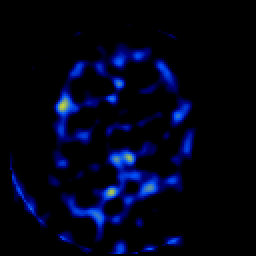

SPECT TL Study #7 -- Slice #43

[Home][Help][Clinical][Tour 1][Tour 2][Tour 3] Slice 43